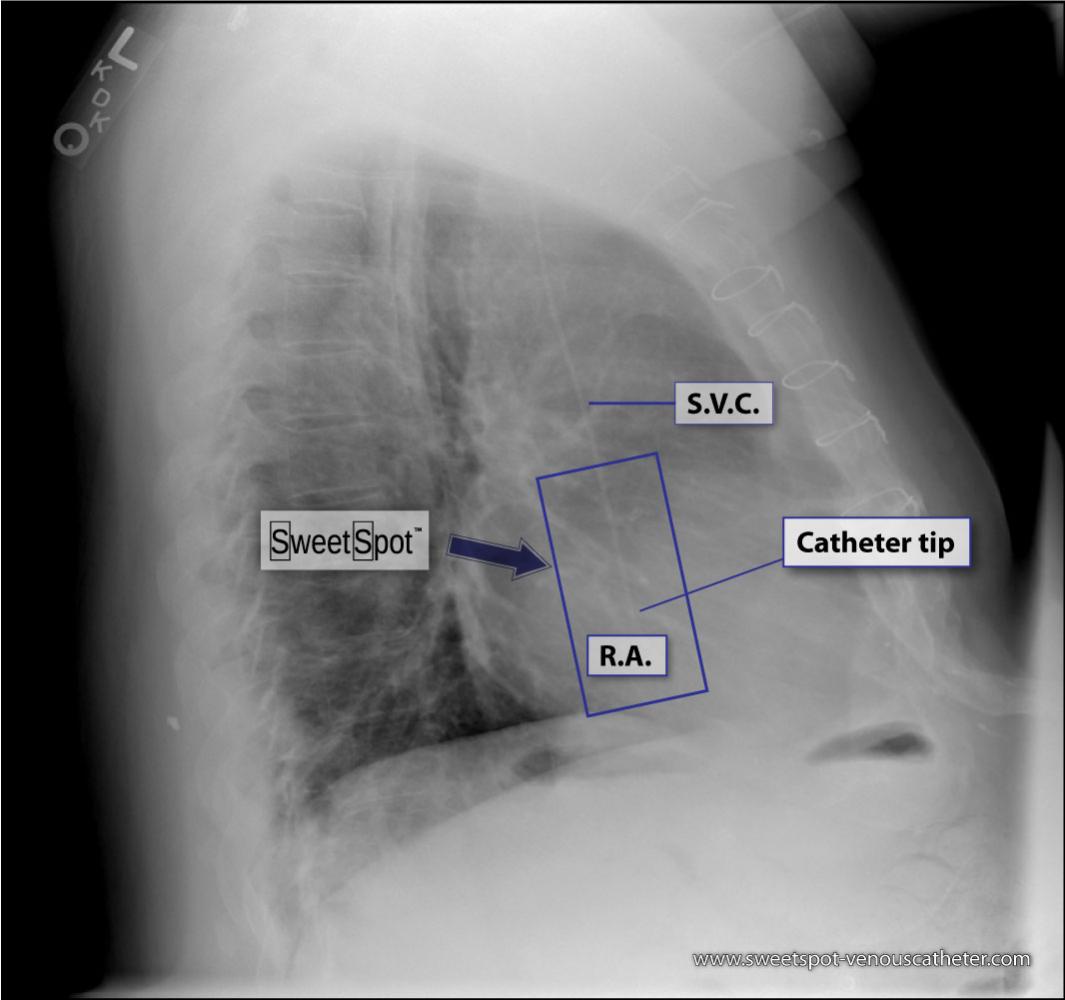

Lateral CXR Sweet Spot™ |

Sagittal CT reconstruction |